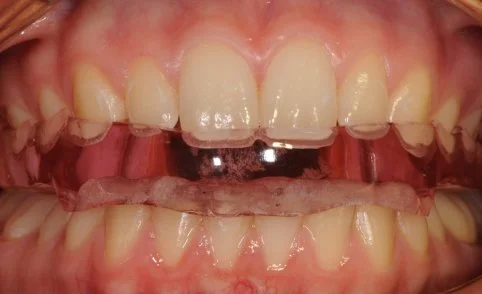

A TMJ Disorder patient requires conservative management with “Full Occlusal Therapy” in 3 stages along with concurrent Full Counselling (refer to journal papers 19 and 20).  In other words, we need to get the disc back into the centre of the joint where it belongs starting with Full Counselling and then a Fully Protective Occlusal Splint (Stage 1).  This splint is made of acrylic resin (used for dentures) and can be made in clear resin but is usually coloured blue or pink to hide any future discolouration (as in the photos below). The splint usually fits the upper teeth and only one is required.

Stage 1 - Fully Protective Occlusal Splint - 4 SA’s over a 3 month period